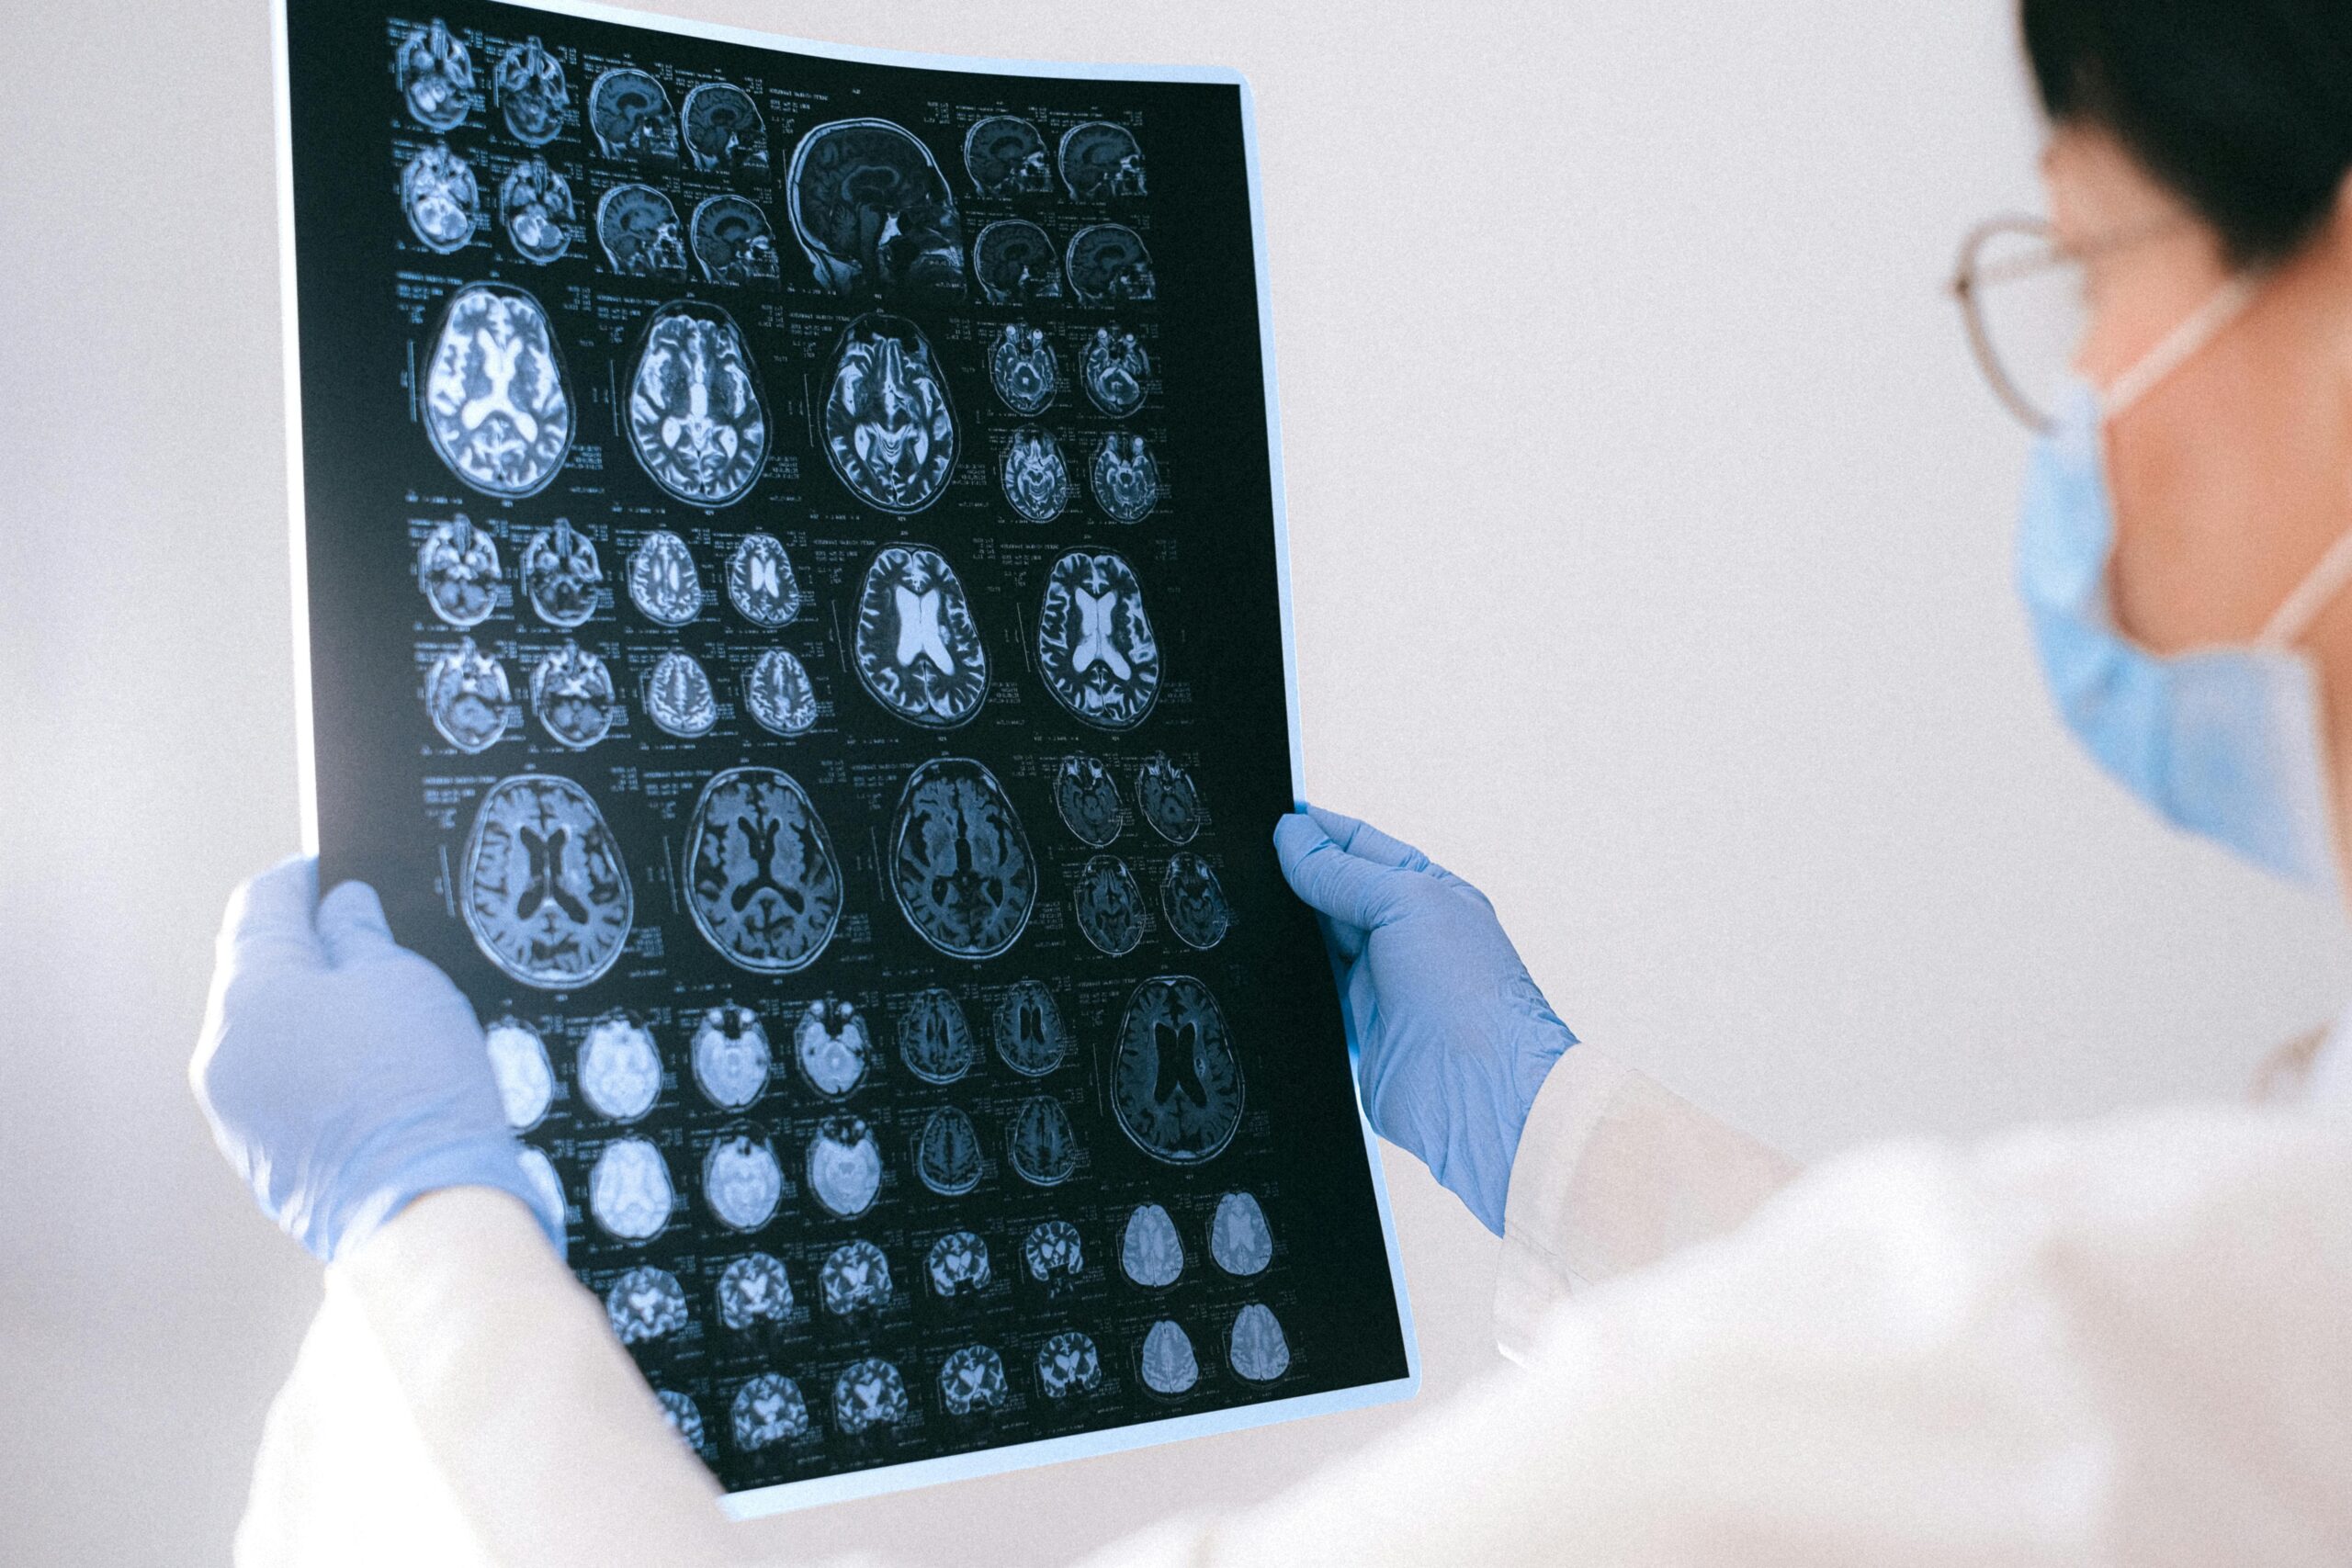

An angio was ordered. Below are sequential DSA images of the left vertebral artery injection. Look at the tremendous hyperemia in the left mesial temporo-occipital area (pink arrows), with physiologic shunting as evidenced by premature appearance of the transverse sinus (blue arrows). This is essentially the picture of parenchymal inflammation — just like any other part of the body, where inflammation makes tissues hot and hypervascular, so it is here. Of course, the differential is any kind of inflammatory/infectious process; in this clinical context, we went with encephalitis.